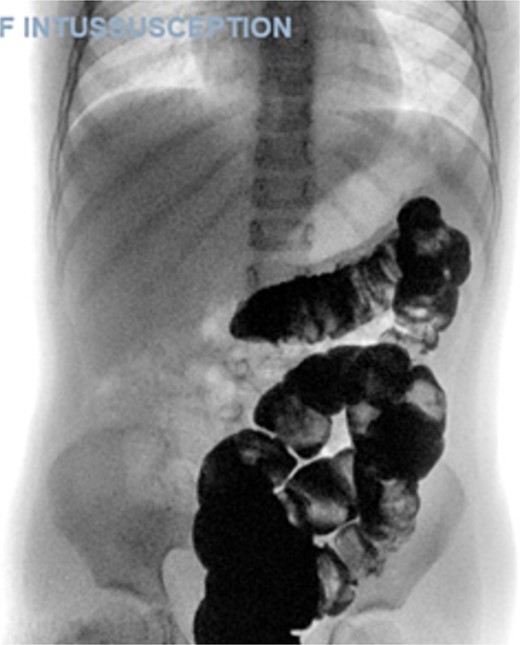

A 5-year-old female presented with a 1-day history of abdominal pain and vomiting. Physical examination revealed abdominal tenderness on the right side. The patient had a history of four previous episodes of intussusception, all of which were conservatively reduced with hydrostatic contrast enema (Fig. 1). The most recent episode occurred 3 months prior to the current presentation. An MRI enterography performed after the fourth episode showed no abnormalities.

The blood tests showed raised inflammatory markers. An abdominal ultrasound confirmed the presence of intussusception (Fig. 2). A decision was made for a laparoscopic reduction of the intussusception and inspecting for a leading point. A MD was demonstrated and resected accordingly (Fig. 3). The location of intussusception was at the ileo-cecal area. The affected bowel was viable. The position of the MD was in the terminal ileum and it was the lead point for the intussusception. No lymph node involvement. Also, a tumor located at the base of the MD ~4 mm from the resection margin, was found and resected.